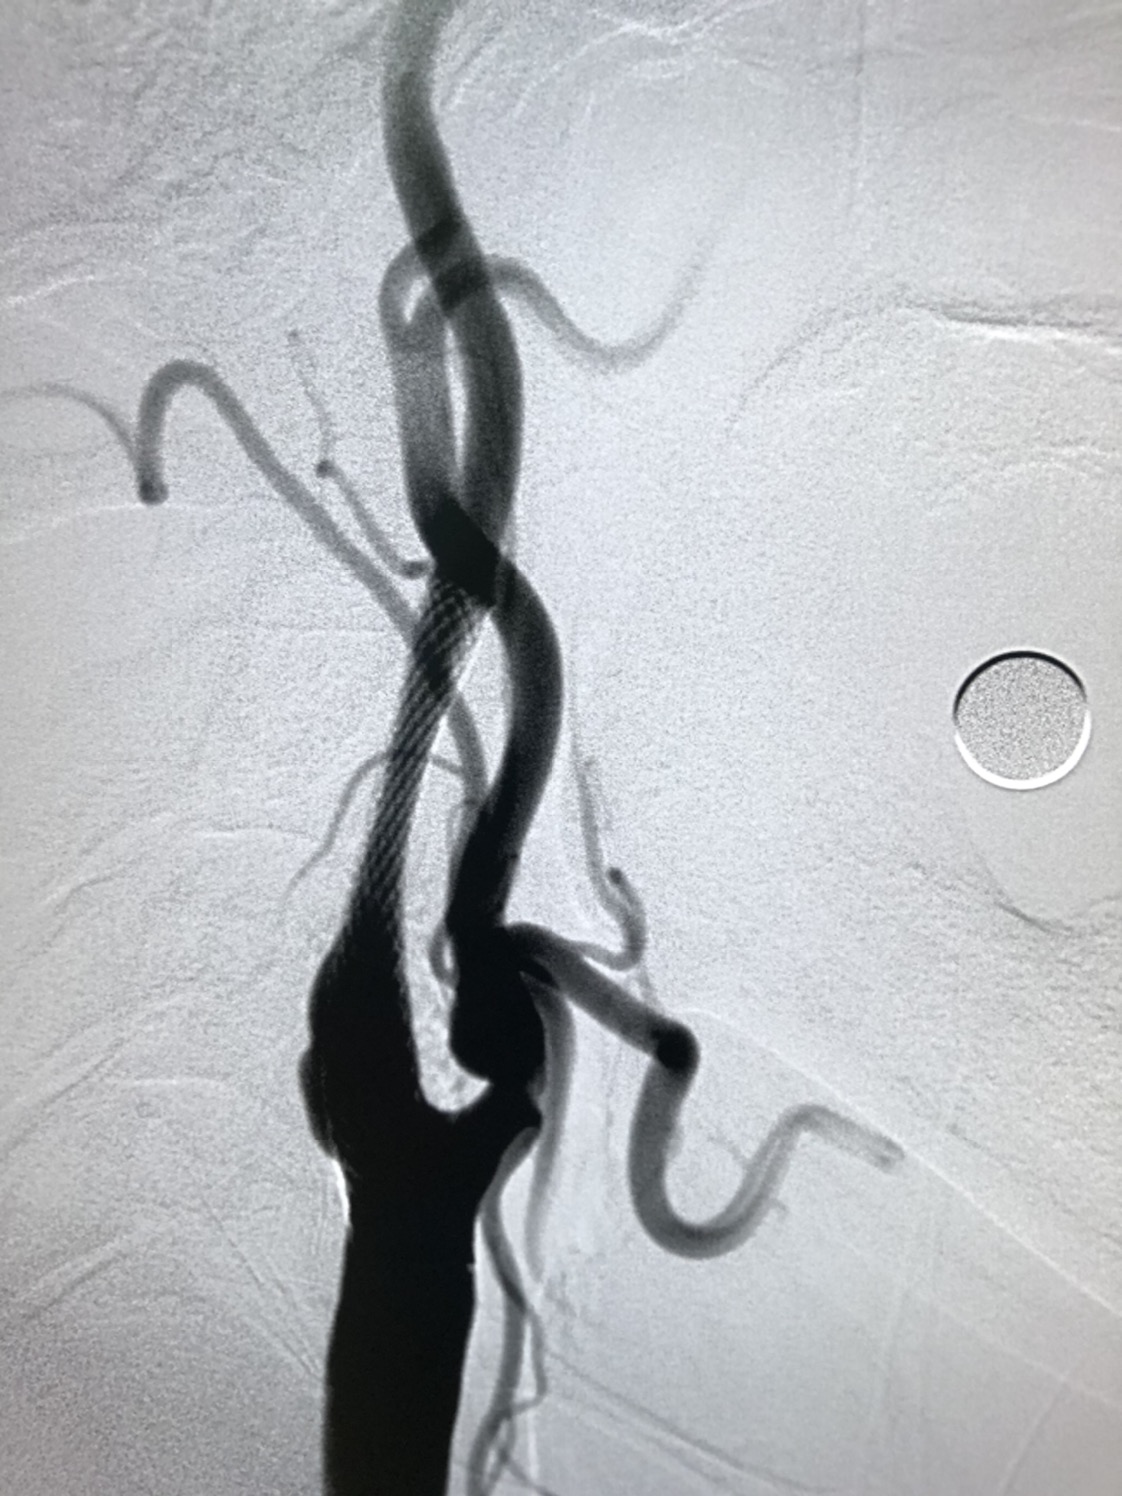

DSA:右侧颈内动脉窦部以远线性狭窄,窦部可见粥样硬化斑块,局部溃疡斑形成,动态可见造影剂滞留,颅内血管显影差。

明确诊断后,考虑患者存在缺血症状,造影提示颈内动脉线性狭窄,同时右侧颈内动脉窦部可见粥样硬化斑块伴溃疡,系患者的罪犯血管。同时因患者后循环血管发育不良,基底动脉纤细伴狭窄,后循环血供均由前循环胚胎型大脑后动脉供应。不积极干预,出现恶性卒中风险极大,因患者颈部较短,且病变部位偏高,建议患者行颈动脉支架成形术。

远端保护伞保护下,4/30球囊预扩后狭窄改善

WALLSTENT 9/40支架定位准确后释放